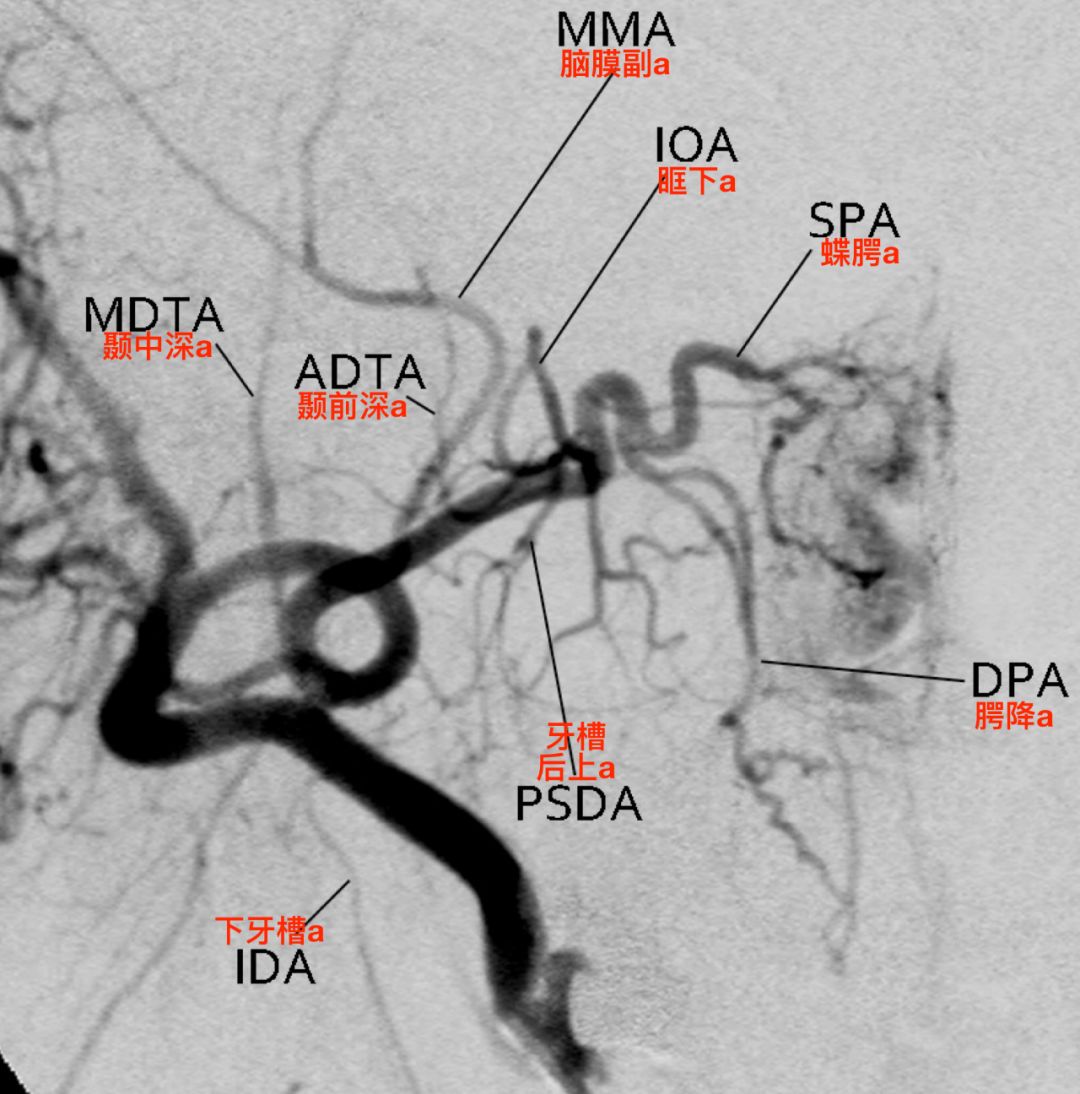

第一段和第二段分支在侧位造影上容易辨认,第三段分支在正位造影上容易辨认。

右侧颈外动脉造影,侧位,显示上颌内动脉的三段及分支(Tanoue 2013)。

![]()

右侧颈外动脉造影,正位,显示上颌内动脉的三段及分支(Tanoue 2013)。